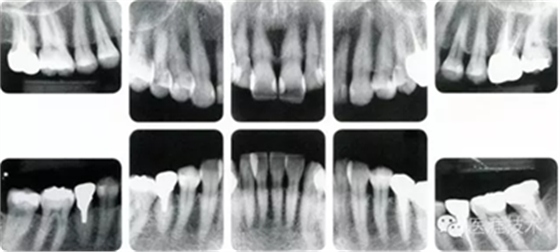

健康且正常的牙周組織臨床圖像

50歲女性的健康口腔內(nèi)部

圖為50歲女性,無(wú)特殊全身疾病,不抽煙。持續(xù)保養(yǎng)6年。無(wú)填充物等問(wèn)題,依照患者本人要求持續(xù)觀察。牙周組織臉頰側(cè)雖見(jiàn)部分萎縮,但X線牙片顯示牙間無(wú)骨吸收現(xiàn)象,保持著比較健康的狀態(tài)。